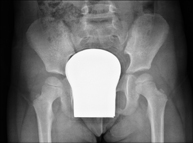

- UIV (Pielografía descendente)

La urografía intravenosa (U.I.V.) consiste en la obtención de imágenes radiológicas seriadas del riñón, de las vías urinarias y la vejiga. Este estudio requiere, siempre, del empleo de un contraste yodado. - Cistografía (CUMS)

La cistouretrografía miccional seriada consiste en la obtención de imágenes radiológicas para valorar la anatomía y la función de la uretra y la vejiga con la administración de contraste yodado a través de una sonda vesical. - Uretrocistografía (Uretro-Cums)

La uretrocistrografía retrógrada y miccional consiste en la obtención de imágenes radiológicas para valorar la anatomía y la función de la vejiga y de la uretra. Se aplica material de contraste a través de una pequeña sonda alojada en la uretra y se obtienen imágenes durante el llenado y vaciado de la vejiga. - Pielografía ascendente por catéter